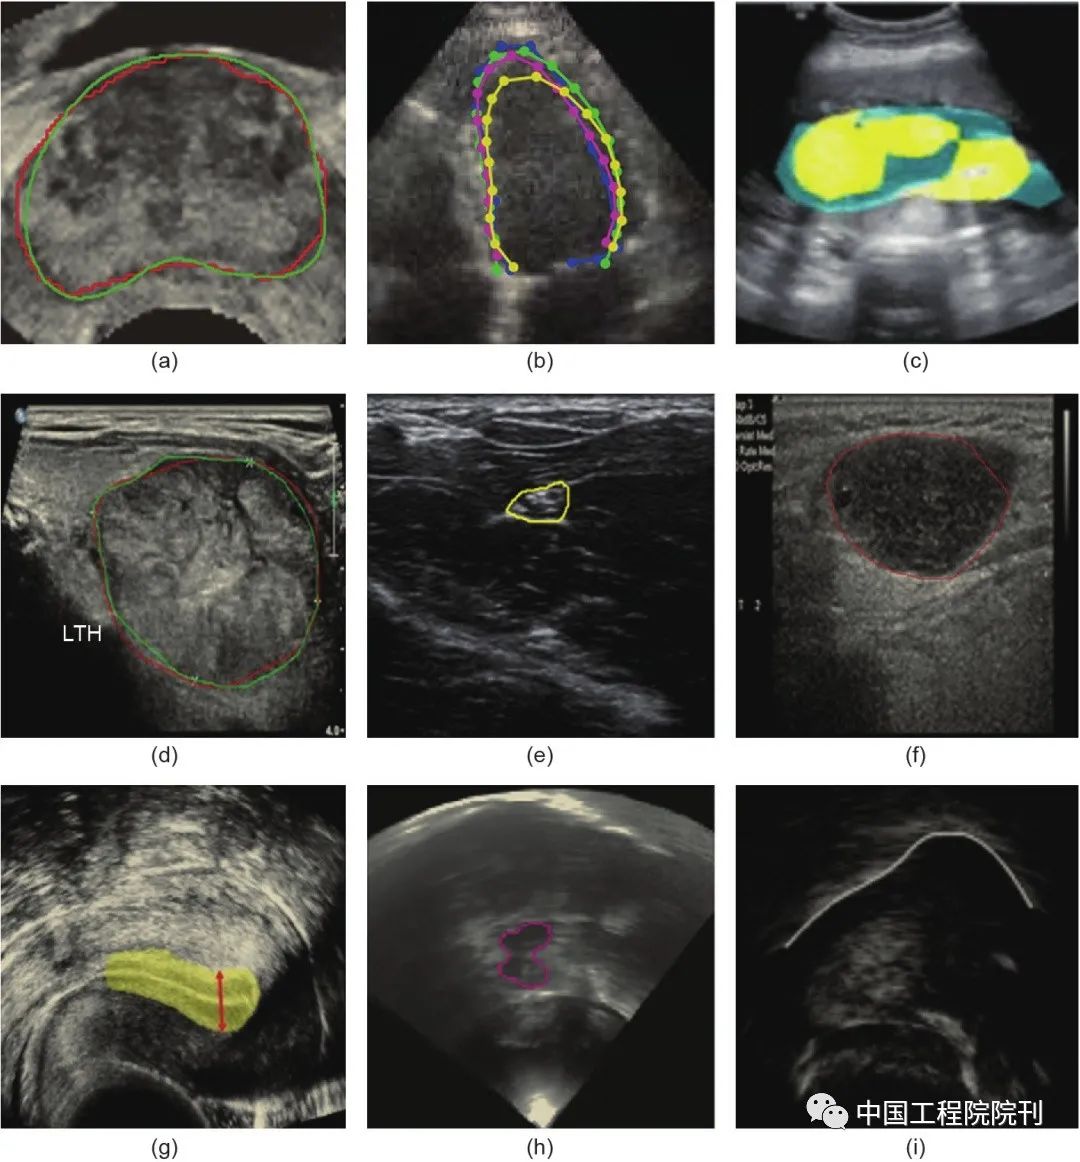

解剖结构与病变的分割是心脏或脑分析中与体积和形状有关的临床参数的量化分析的前提条件,在病变(如乳腺、前列腺、甲状腺结节与肺结节)的检测与分类,以及生成ROI以便在CADx中进行后续分析方面也起着至关重要的作用。由于超声图像中目标与背景之间的对比度较低,对大部分解剖结构,尤其病变(结节)超声图像进行准确的分割,仍然是一个很有挑战性的任务。此外,众所周知,手动分割方法是非常耗时耗力的,且存在很大的个体差异。因此,很有必要开发更先进的自动分割方法来解决这些问题。使用深度学习进行解剖结构分割的一些结果如图5所示。

图5 使用深度学习进行常见解剖结构分割的分割结果示例。(a)前列腺;(b)左心室;(c)羊水与胎儿身体;(d)甲状腺结节;(e)中神经结构;(f)淋巴结;(g)子宫内膜;(h)中脑;(i)舌轮廓。所有这些结果都表明了与人类放射科医生相当的分割性能。不同颜色的线或点表示相应的分割轮廓或区域